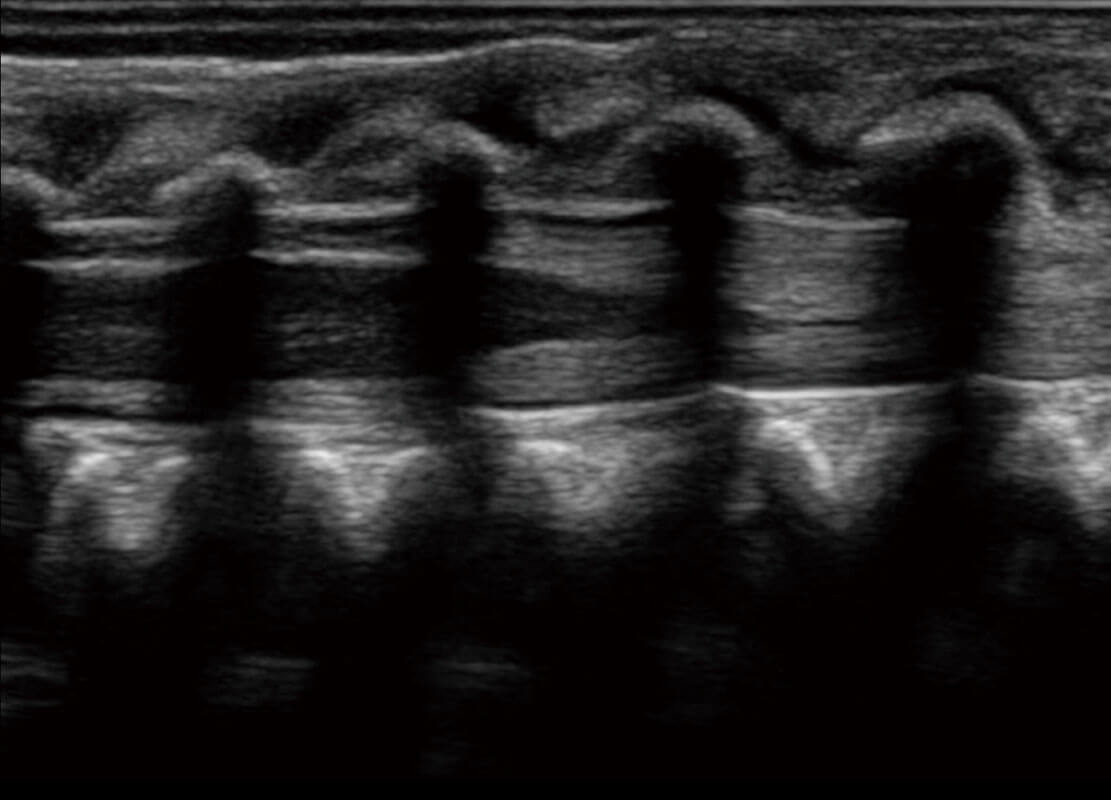

新生儿脊髓圆锥

P60搭载宽频带线阵探头、宽景成像、弹性成像技术,为您提供乳腺应用方案。P60支持高频相控阵探头、线阵探头、腹部高频探头、腹部微凸探头等,丰富的探头群搭载敏感的彩色血流成像,适用于新生儿多种脏器检测要求,满足新生儿筛查需求。